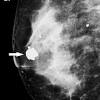

Clinical And Pathological Features Of Breast Cancer In A Population Of Mexico Cirugia Y Cirujanos English Edition

Clinical And Pathological Features Of Breast Cancer In A Population Of Mexico Cirugia Y Cirujanos English Edition from multimedia.elsevier.es